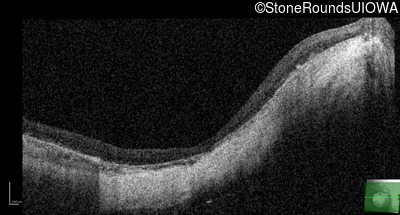

Age at visit: 15 years

This 15 year old male had a macular abnormality noted two weeks ago when he was refracted for his first pair of glasses. Bone spicule-like pigmentation was first noticed a year later (age 16) during a routine follow-up eye exam.